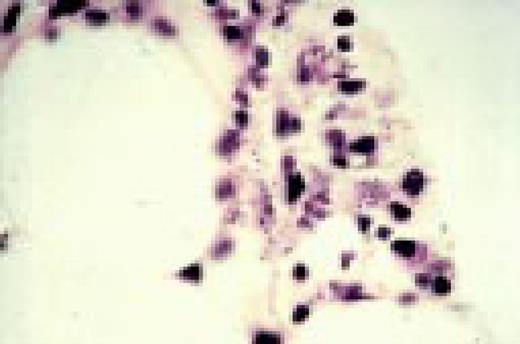

Slide L49

HIV-associated lymphadenopathy, lymph node, H&E. Multinucleated cells are clearly appreciated, as is a venule.FIG49